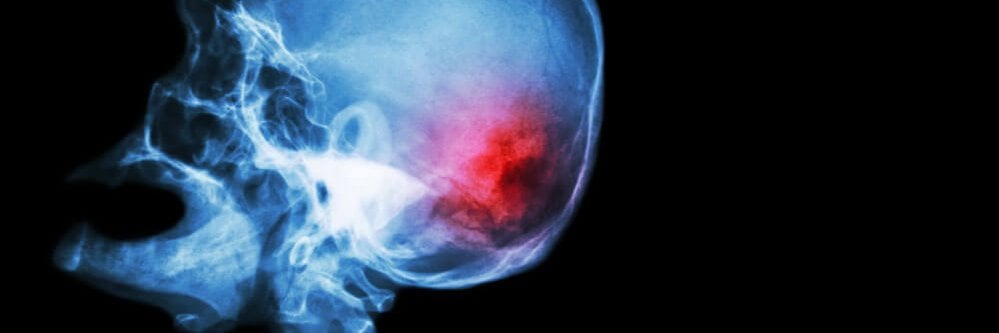

קיימים חלקים בגוף היוצרים דחף חשמלי לחוט השדרה או למוח ובכך מאפשרים לגופנו לנוע ולחוש תחושות מסוימות. נוירונים חושיים מאפשרים לנו לחוות טמפרטורה, טעם וצליל.

לאור האמור, ברור לכול כי פגיעה עצבית עלולה לשנות את חיינו בתכלית.

חלקים זעירים אלה בגוף נושאים באחריות עצומה כשהם מעבירים דחפים חשמליים לחוט השדרה או למוח, ומאפשרים לגופכם לנוע ולהרגיש. נוירונים חושיים מאפשרים לכם לחוות טמפרטורה, טעם וצליל.

עצבי ממסר ונוירונים מוטוריים מנהלים את ההודעות ממערכת העצבים המרכזית שלך לאזורים שונים בגופך, כמו הידיים והרגליים שלך, המאפשרת לך לנוע. כאשר הם נפגעים, התוצאות יכולות להיות משנות חיים.